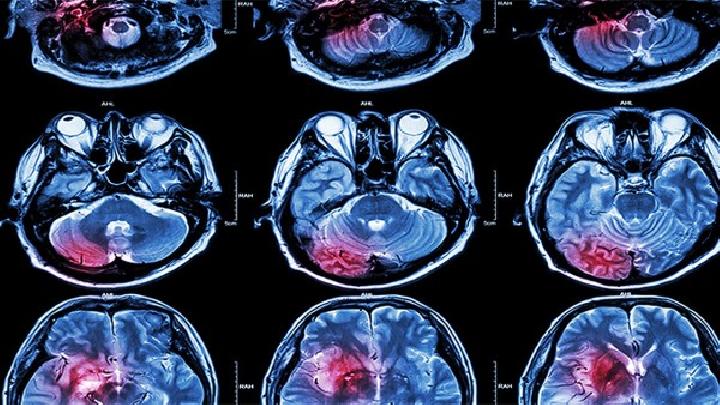

4、MRI可显示或轻或重的结构损伤